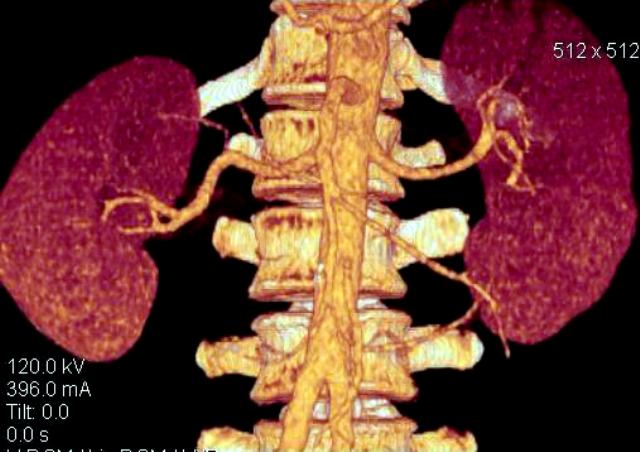

КТ Ангио почечных артерий.

Добавочные почечные артерии.

Справа добавочная артерия, питающая верхний полюс почки. Отходит от основного ствола почечной артерии. Слева дополнительная артерия, питающая нижний полюс почки, отходит от брюшной аорты, несколько выше бифуркации. В аорте видны атеросклеротические бляшки, одна из них довольно близко к устью добавочной артерии. Это может иметь клиническое значение.